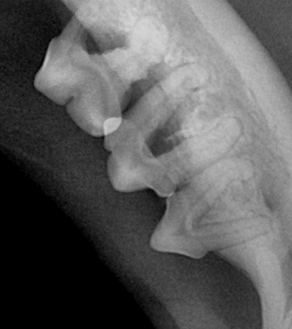

치주염은 진행 정도에 따라 1~4기로 분류되며, 기수에 따라 관리 방법과 치료 방향이 달라집니다.

| 1기 (경도) | 잇몸 가장자리에 염증 발생 | 입 냄새 시작, 이빨 누르면 잇몸 붉어짐 |

| 2기 (중등도) | 염증이 치아 주변까지 확산 | 냄새 심해짐, 딱딱한 사료 꺼림 |

| 3기 (중증) | 치아 지지 조직 파괴 시작 | 이빨 흔들림, 침 흘림 |

| 4기 (중증 이상) | 치아 탈락, 고름, 턱뼈 침범 가능성 | 심한 통증, 입 주변 부음, 만성 염증 |